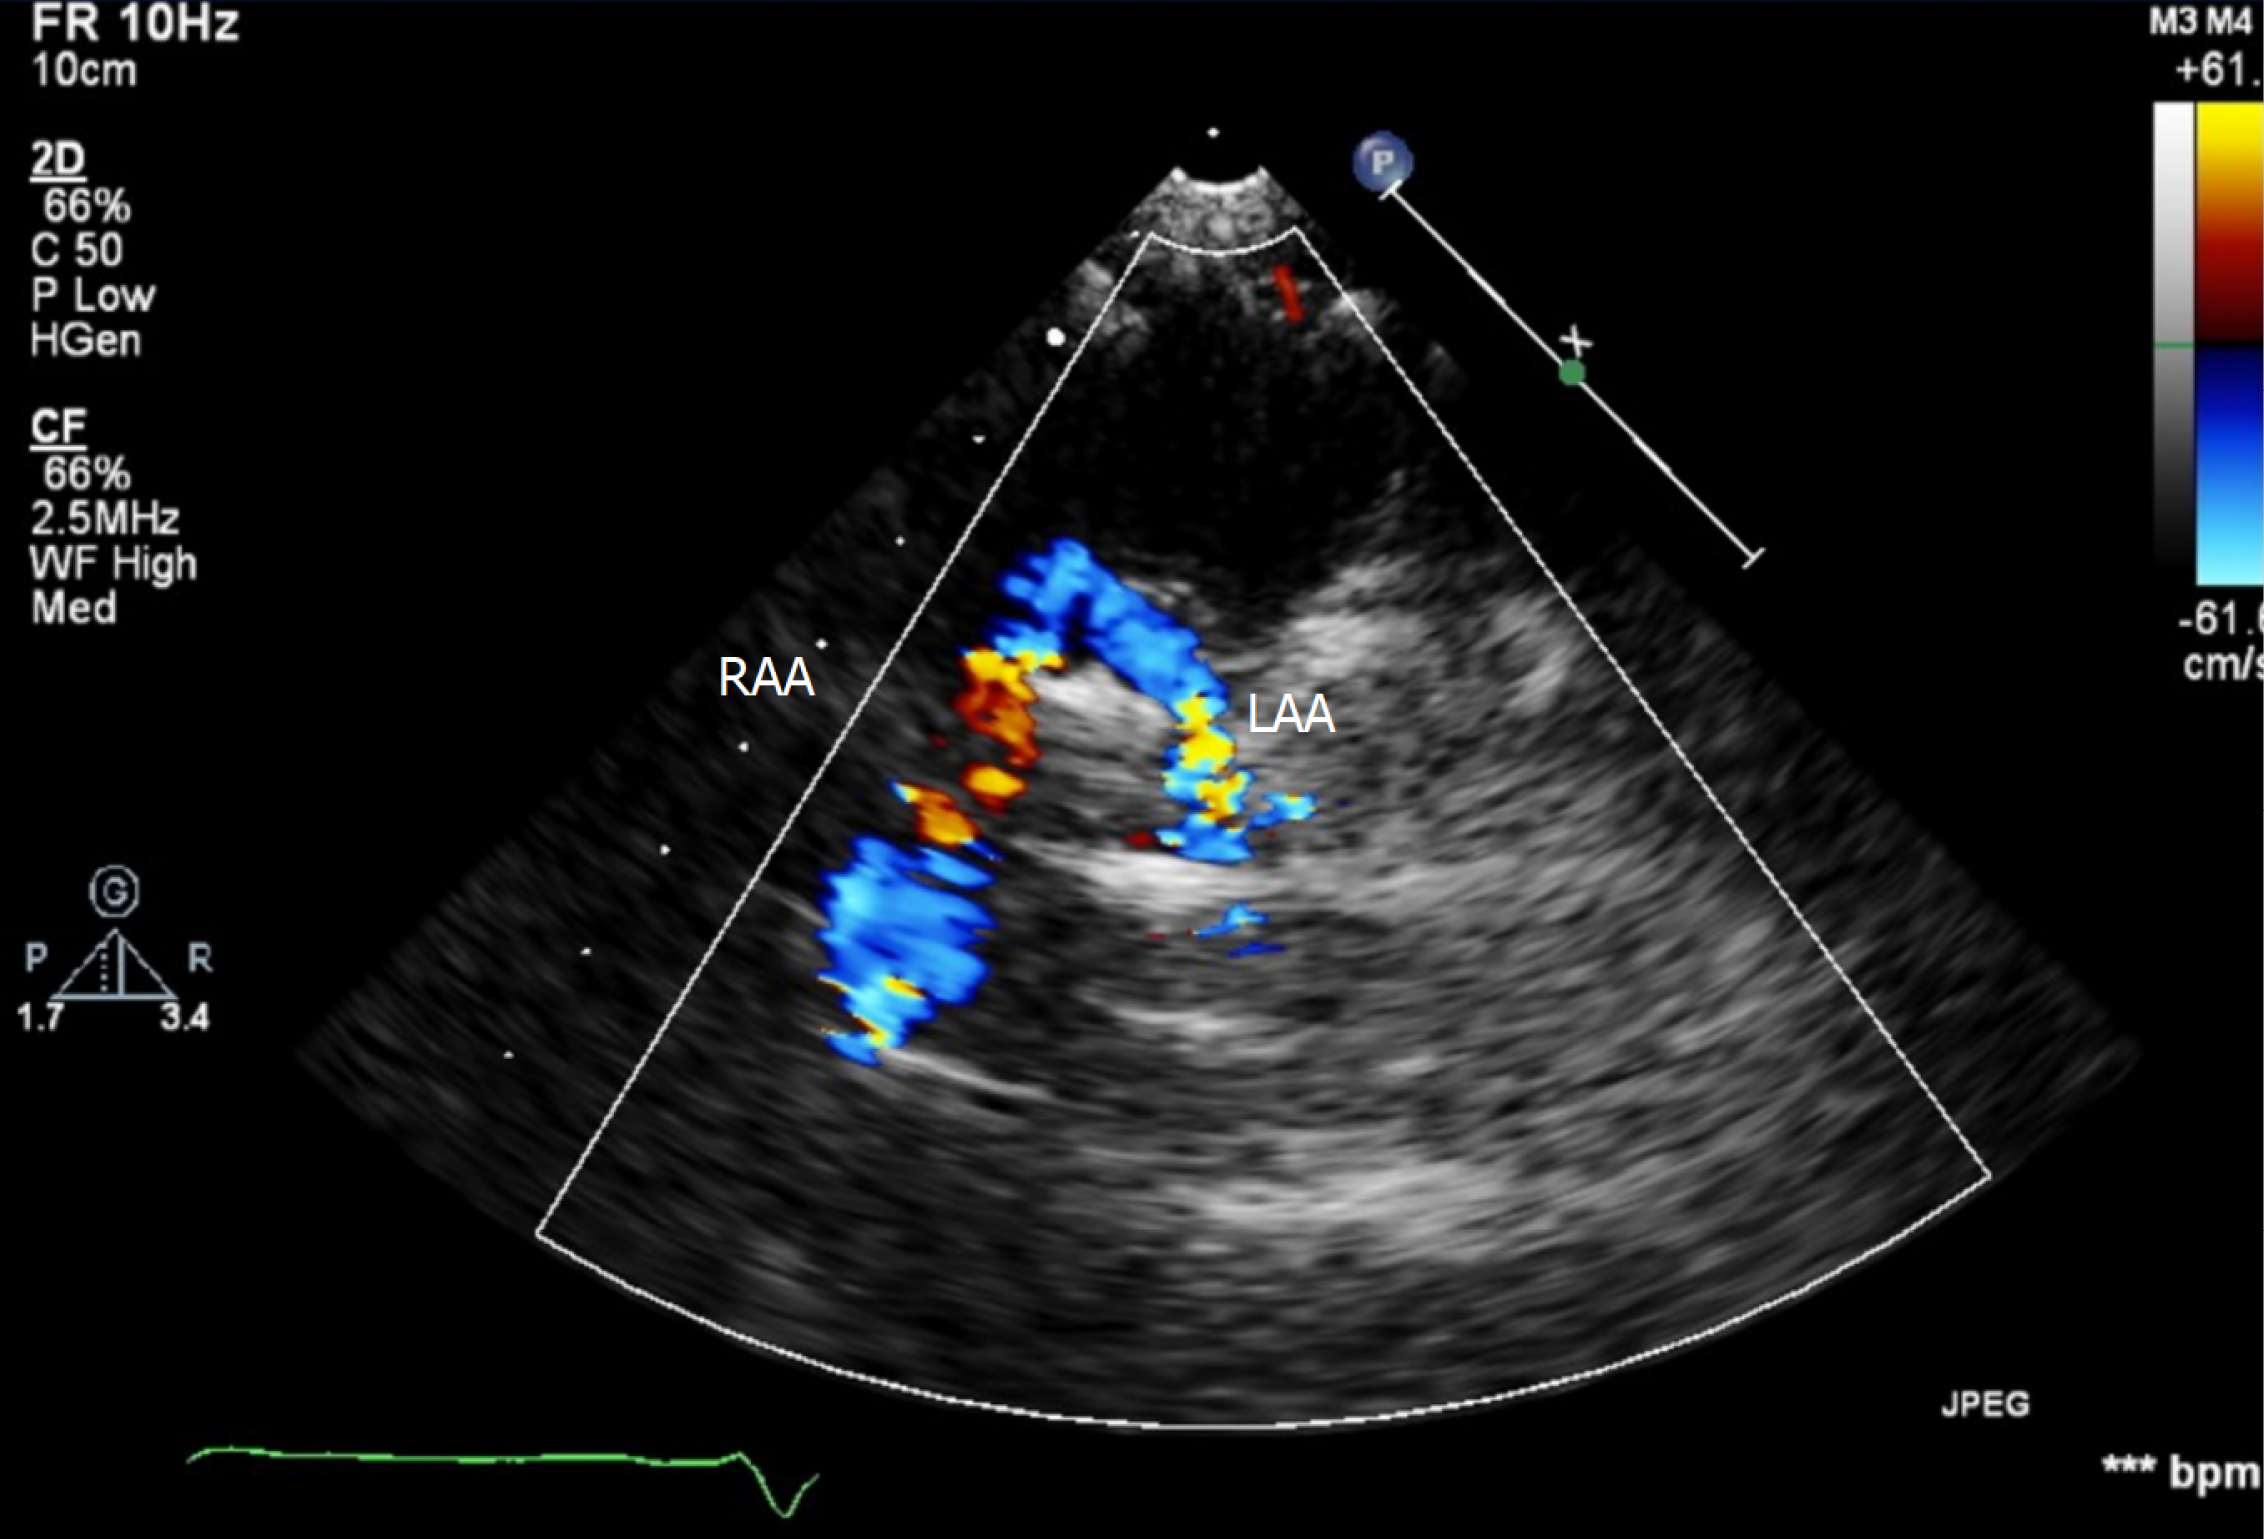

Figure 1 illustrates the echocardiographic findings of a 38-month-old patient with DAA, and Figure 2A shows the corresponding chest radiograph. Notably, this patient had previously been diagnosed with asthma and experienced recurrent respiratory infections requiring multiple antibiotic courses and repeated hospitalizations prior to definitive diagnosis.

All patients underwent preoperative TTE and CTA for anatomical delineation (Figures 3 and 4). One patient additionally underwent diagnostic cardiac catheterization (Figure 2B).